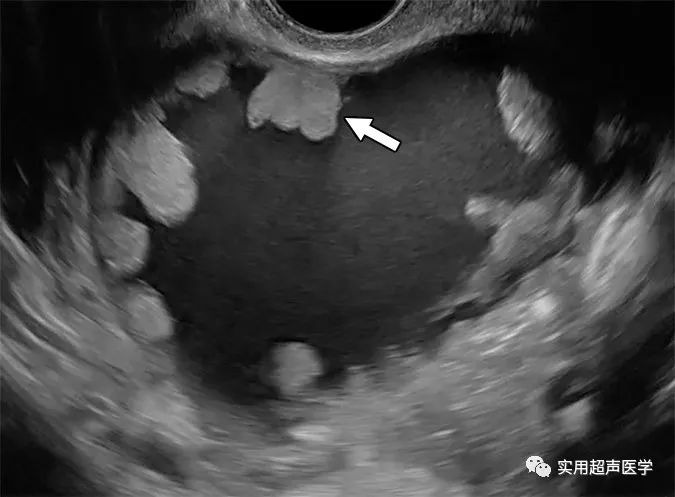

35岁女性,右下腹胀满,边缘性浆液性囊腺瘤。超声图像显示单房囊肿,有多个状突起(箭头)。评估是卵巢-附件报告和数据系统 (O-RADS) 类别 5。状突起代表突出到囊肿腔的固体成分的亚型,高度至少为 3 mm,三面被液体包围。状投影在其与附着的壁或隔膜的界面处具有锐角,而固体成分呈钝角并呈现无柄。状投影的数量有助于O-RADS风险类别评估,四个或更多状投影赋予更高的恶性肿瘤风险。